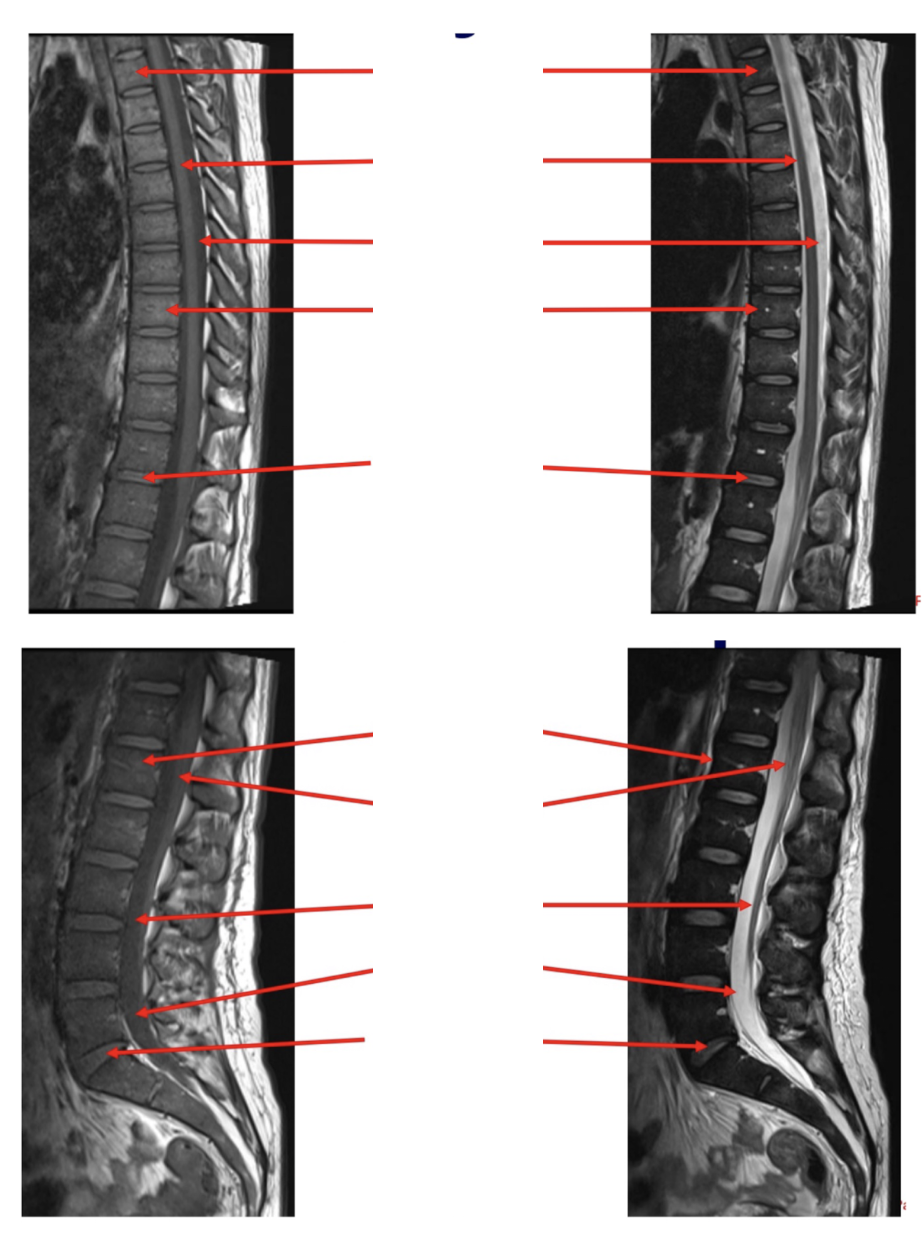

Sequence + Pathology?

T1,T2

• Cauda Equina syndrome

• L5/S1 disk space herniation compressing the cauda equina.

• Signal intensity is lost in T2 sag as you get to L5/S1 disk space.

New cards

Sequences + pathology?

• Axial=T2,1st sag=T1,2nd sag=T2

• Anterior disk bulge of L3/4 and L4/5 disks

• Anterior longitudinal ligament has lost its normal shape as it is being pushed

anteriorly by the disk bulges.

Pathology?

• Vertebral tumour that has invaded the spinal cord

Sequences + Pathology

• T2, T2FS, T1C+

• Path = multiple sclerosis

• Increased signal within the spinal cord confirming the presence of lesions